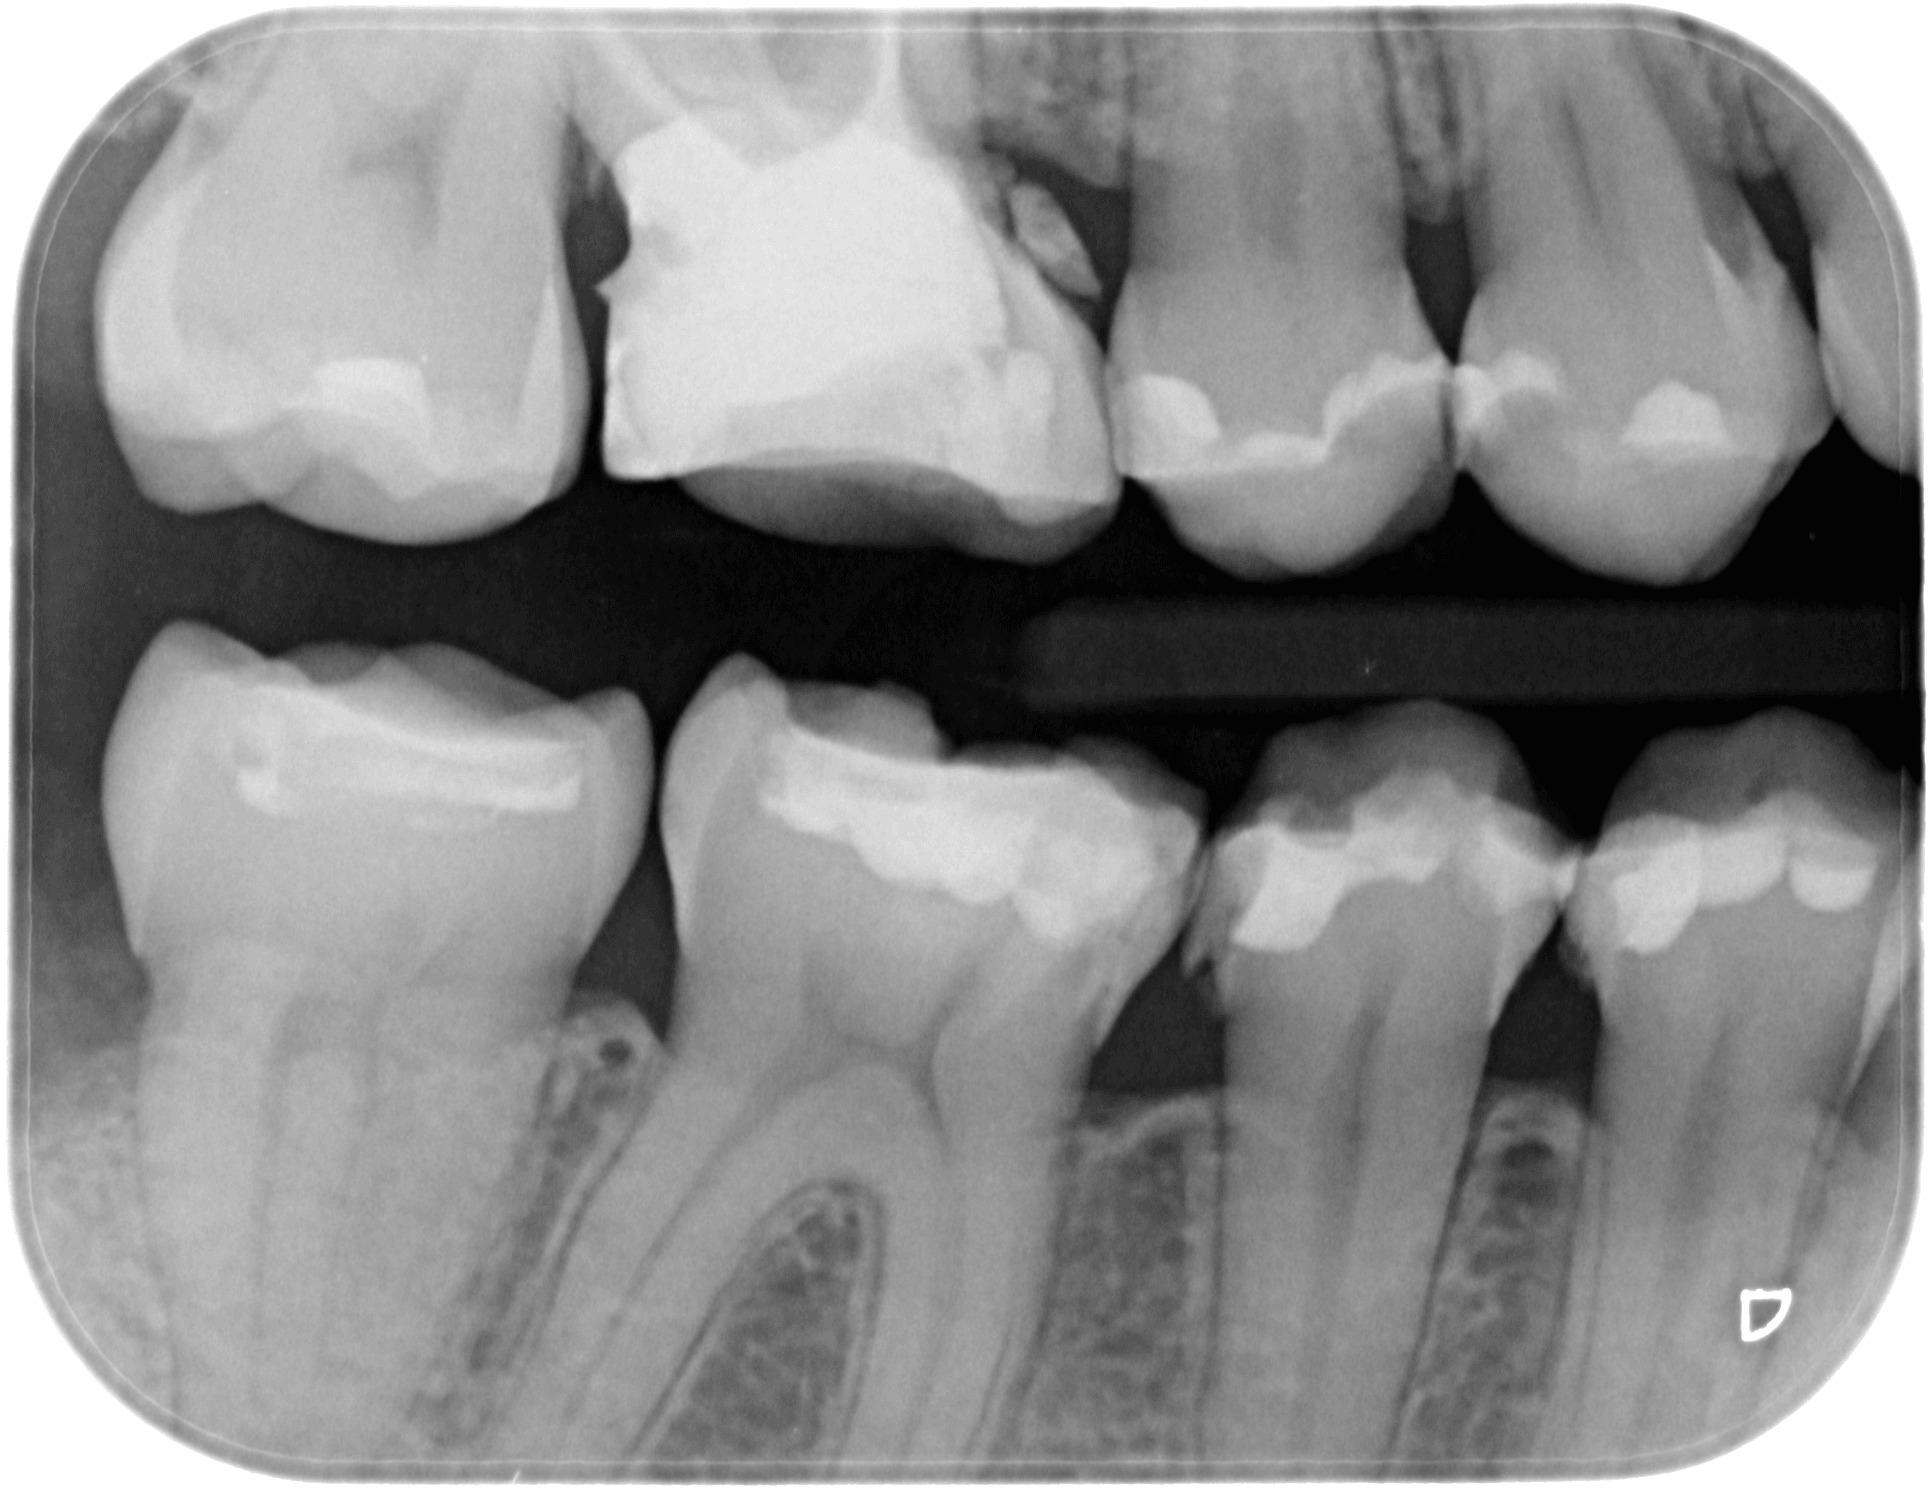

Байтуинг (Bitewing)

Байтуингът е един от методите за диагностициране на кариес в междузъбните контакти едновременно на горните и долните странични зъби. С негова помощ се констатира и загуба на костно вещество при пародонтит. За направата му се използва специален държател, който улеснява позиционирането.